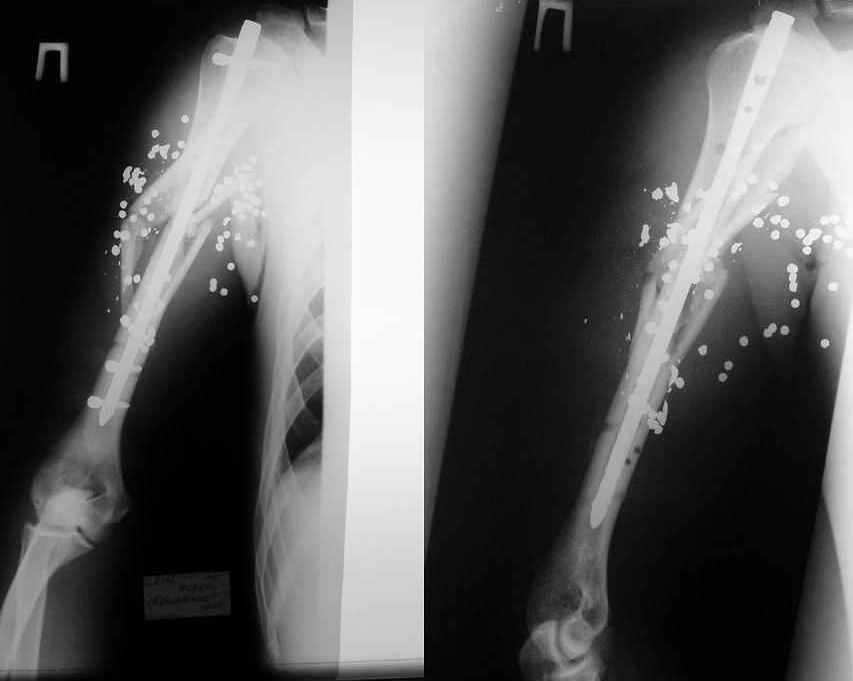

Re: Огнестрельный перелом плеча ( продолжение)

Alexander Chelnokov 11 Август 2006, 20:06

ММВ> выполнен закрытый блокируемый остеосинтез. Клинически результатом

ММВ> доволен. Рентгенологически - не вполне. нужно было погрузить стержень

В целом можно поздравить, очень неплохо. Рассверливали ли канал? Вверху вроде один винт, и в динамическом отверстии - лучше бы в статическое, а то стержень можт еще вылезти. А что за стерюень? Похоже на ChM. Из-за того, что выстоит, либо придется удалять рано или поздно. Либо через 2-3 мес. сделать ревизию - извлечь фиксатор, канал немного углубить и рассверлить, и тот же стержень ввести уже поглубже.

В дистальном отделе хватит и одного винта, лучше переднезаднего, чтобы поберечь лучевой нерв.

Канал не рассверливал. Стержень 7мм.ChM. В статическое отверстие не стал вводить винт, побоялся попасть в пустоту, а зря. Лучевой нерв видел,когда вводил дистальные винты. Антибиотики сменены, но складывается впечатление, что они не нужны.